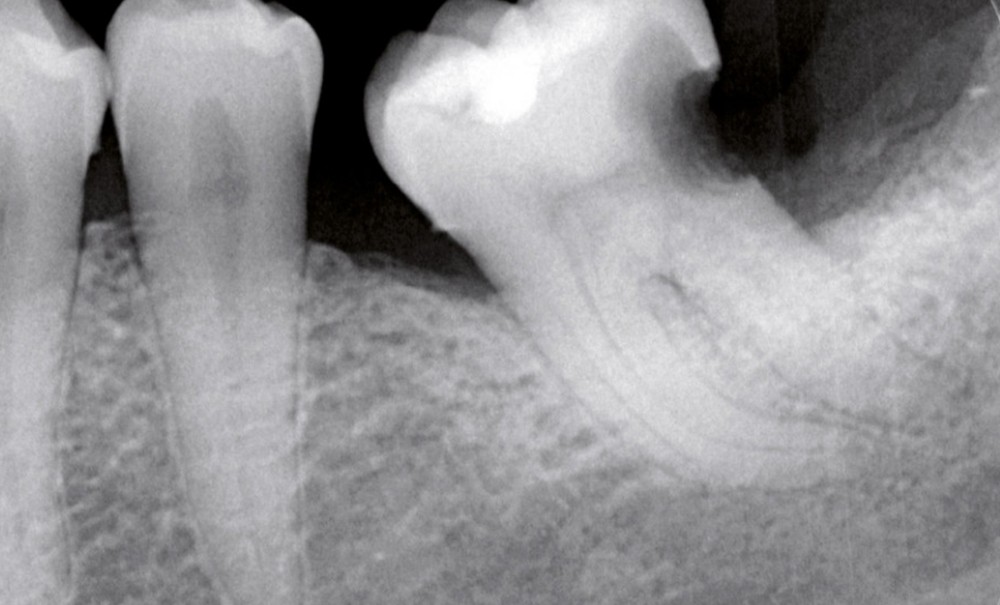

Connus depuis le milieu des années 1990 en endodontie [1-3], les biocéramiques continuent de trouver de nouvelles applications. Alors qu’ils ont été longtemps réservés aux traitements des perforations, aux techniques d’apexification ainsi qu’à l’obturation rétrograde, ces matériaux sont désormais disponibles pour l’obturation orthograde.

L’obturation est une étape clé du traitement endodontique, et fait partie intégrante de la célèbre triade endodontique : désinfection, mise en forme, obturation. Le concept de l’obturation dite « classique » repose essentiellement sur deux protagonistes : un matériau de remplissage, qui est là pour occuper un maximum de place dans l’endodonte, et un matériau de scellement, qui sert à faire le joint entre le matériau de remplissage et la dentine.

Dans les techniques d’obturation utilisées aujourd’hui, la gutta-percha joue le rôle du matériau de remplissage, et le ciment (qu’il soit à base d’oxyde de zinc-eugénol, de résine époxy, d’hydroxyde de calcium…) celui du matériau de scellement. Le ciment représente malheureusement le point faible de l’obturation. En effet, celui-ci est, d’une part soumis à une rétraction de prise après sa mise en place [4-6], et d’autre part à une réaction d’hydrolyse et ce, même après la prise [7,8]. Étant donné que le ciment sera forcément en contact avec un milieu humide, ne serait-ce qu’avec les fluides péri apicaux au niveau du foramen, cette dégradation est inévitable et conduit à la percolation…